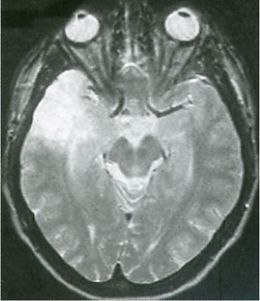

Figura 1. Corteza cerebral. Nótese el engrosamiento de la sustancia gris cortical y la mala definición entre la sustancia gris y la sustancia blanca.

En la mayoría de los casos la DCF, como su nombre lo indica, se halla restringida a una o dos circunvoluciones que aparecen ensanchadas y de aspecto anormal (disgiria) en cualquiera de los lóbulos cerebrales, más frecuentemente en el lóbulo temporal.

Al corte, la sustancia gris puede estar engrosada; la zona de unión con la sustancia blanca muestra límite impreciso, borroso, difícil de establecer con exactitud, a veces puede haber islotes ectópicos de sustancia gris en la blanca.